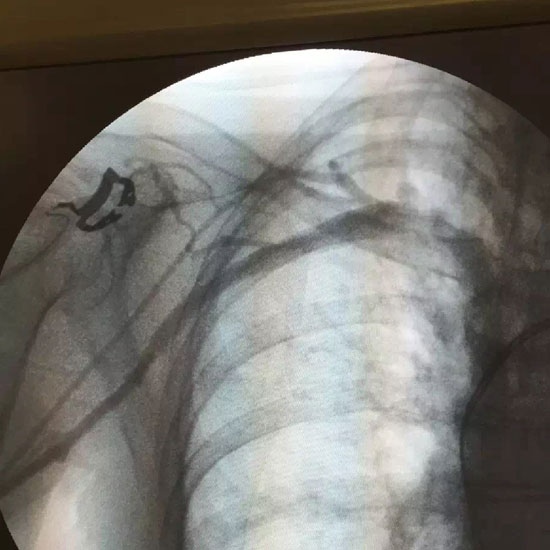

• 医疗影像。刘秀实供图